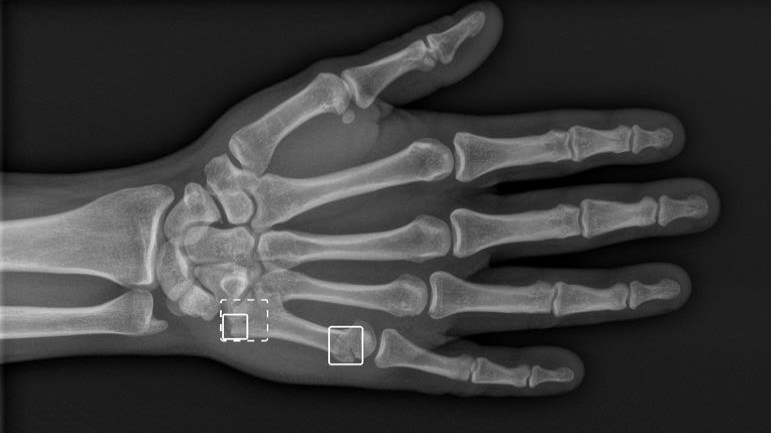

Nu skal kunstig intelligens være med til at afgøre om der er knoglebrud på under et minut. Den nye løsning skal minimere flaskehalse på skadestuer og i skadeklinikker.

Nu afgør kunstig intelligens om en skadestuepatient har et knoglebrud i arme eller ben. Den kunstige intelligens kan med meget stor sikkerhed afgøre, om der er et brud ud fra et røntgenbillede. Det bruges til at vurdere, hvilke patienter der skal ses først, og om nogle kan sendes hjem igen.

En stor del af de patienter, hvor der mistænkes knoglebrud, får i dag foretaget røntgenundersøgelser for at afklare eventuelle brud. Det skaber en flaskehals på skadestuerne, når røntgenbillederne skal aflæses og fortolkes.

Region Nordjylland har derfor nu implementeret løsningen, der med meget høj grad af sikkerhed kan afgøre, om der er tale om brud eller ej på røntgenbillederne.

Svaret på røntgenundersøgelsen kommer derfor nu inden for 1 minut efter, at billedet er taget. I første omgang er systemet taget i brug i skadestuen på Aalborg Universitetshospital og på skadeklinikken i Farsø. Det er planen, at alle regionens akutmodtagelser og skadeklinikker skal have systemet på sigt.